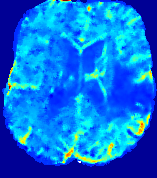

4.3.1 Advection Imaging via Advection-Diffusion

Slice #1Slice #2Slice #3Slice #4Slice #5Slice #6𝐕gt𝟐subscriptnormsuperscript𝐕gt2\|\bf{V}^{\text{gt}}\|_{2}Refer to captionRefer to captionRefer to captionRefer to captionRefer to captionRefer to caption𝐕est𝟐subscriptnormsuperscript𝐕est2\|\bf{V}^{\text{est}}\|_{2}Refer to captionRefer to captionRefer to captionRefer to captionRefer to captionRefer to captionRefer to caption1.51.51.51.21.21.20.90.90.90.60.60.60.30.30.30.00.00.0(mm/s)𝑚𝑚𝑠(mm/s)Destsuperscript𝐷estD^{\text{est}}Refer to captionRefer to captionRefer to captionRefer to captionRefer to captionRefer to captionRefer to caption0.0150.0150.0150.0120.0120.0120.0090.0090.0090.0060.0060.0060.0030.0030.0030.0000.0000.000(mm2/s)𝑚superscript𝑚2𝑠(mm^{2}/s)

Figure 14: PIANO identifiability testing: advection imaging via advection-diffusion. Top row shows 𝐕gt2subscriptnormsuperscript𝐕gt2\|{\bf{V}}^{\text{gt}}\|_{2} used for simulating ground truth pure advection. Rows below show the estimated 𝐕est2subscriptnormsuperscript𝐕est2\|{\bf{V}}^{\text{est}}\|_{2} and Destsuperscript𝐷estD^{\text{est}} on corresponding slices. Note that the plotted value scale for Destsuperscript𝐷estD^{\text{est}} is 0.01 of that for 𝐕gt2subscriptnormsuperscript𝐕gt2\|{\bf{V}}^{\text{gt}}\|_{2} and 𝐕est2subscriptnormsuperscript𝐕est2\|{\bf{V}}^{\text{est}}\|_{2}.

We use the same ‘Advection Imaging’ simulation of Sec. 4.2.1 as the concentration dataset for PIANO. However, instead of modeling pure advection (Eq. 15), we let PIANO estimate both velocity 𝐕estsuperscript𝐕est{\bf{V}}^{\text{est}} and diffusivity Destsuperscript𝐷estD^{\text{est}} via the advection-diffusion PDE (Eq. 2) underlying the proposed PIANO model. Fig. 14 shows the estimated 𝐕est2,subscriptnormsuperscript𝐕est2\|{\bf{V}}^{\text{est}}\|_{2}, and Destsuperscript𝐷estD^{\text{est}} fields for one patient. Although PIANO has the freedom to estimate both a velocity and a diffusivity field from pure advection, PIANO differentiates well between advection and diffusion: the estimated 𝐕est2subscriptnormsuperscript𝐕est2\|{\bf{V}}^{\text{est}}\|_{2} successfully reproduces the ground truth 𝐕gt2subscriptnormsuperscript𝐕gt2\|{\bf{V}}^{\text{gt}}\|_{2} governing the simulated advection process, just as it already did in the ‘Advection Imaging via Advection’ test (Fig. 12). More importantly, the estimated diffusivity Destsuperscript𝐷estD^{\text{est}} is orders of magnitudes smaller than 𝐕est2subscriptnormsuperscript𝐕est2\|{\bf{V}}^{\text{est}}\|_{2}, indicating the estimated diffusion is negligible compared to the estimated advection, which is highly consistent with the underlying pure advection of the simulated data.